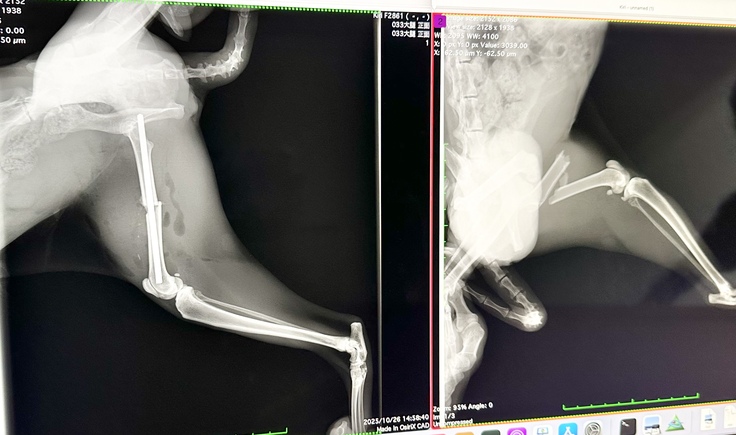

昨日保護した母猫 祥(さち)

本日手術をしていただき、先程面会に行ってきました!!

左足負傷して10日目ですが、骨折端に肉芽が巻き付いて骨が動かないほどガチガチだったそうです。

巻き付いた肉芽を丁寧に剥がしてピンで固定していただきました。

術後1ヶ月はケージ内で安静にしなければなりませんが、骨折の状態次第でフリーにできるそうです。

痛みを取り除いてあげることができて本当に良かったです。これからは、何の心配もなく親子仲良く過ごさせてあげたいですね☺️